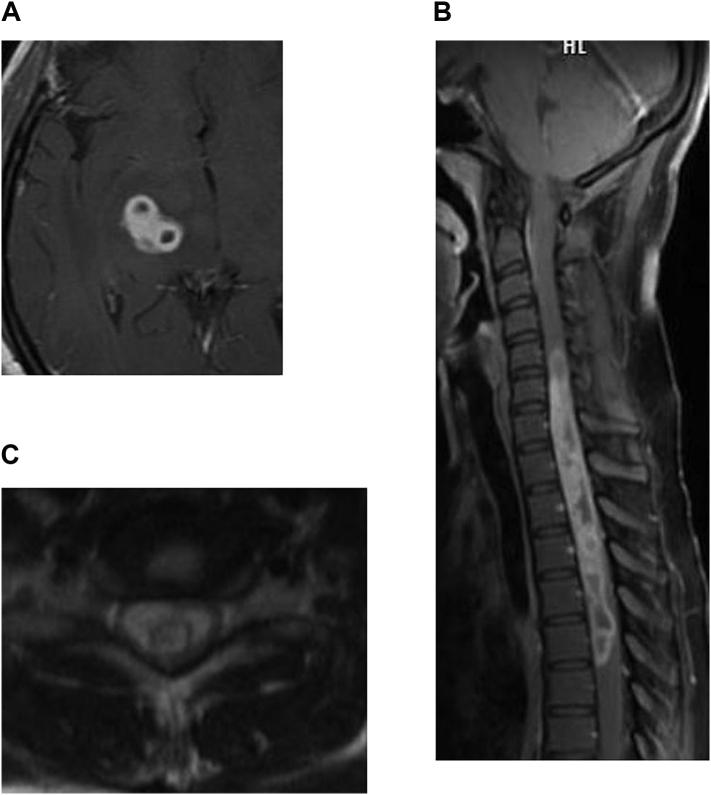

MRI findings in tubercular radiculomyelitis.

This article aims to familiarize the reader with the MR imaging findings of tubercular radiculomyelitis (TBRM) and to identify the sources of infection. We evaluated 29 patients on a 1.5 T GE MRI in a cross-sectional study. MRI of the spine with contrast and lumbar puncture were performed in all patients. MRI brain was performed for 13 patients. The typical and atypical manifestations enlisted in this article, will enable early detection of TBRM when the clinical history is ambiguous, as TBRM can present with low backache in both retrovirus positive and negative patients.

本文旨在使读者熟悉结核性脊神经根脊髓炎(TBRM)的磁共振成像(MR)表现,并确定感染源。在一项横断面研究中,我们对29例患者进行了1.5T通用电气(GE)磁共振成像检查。所有患者均接受了脊柱增强磁共振成像检查和腰椎穿刺。13例患者进行了脑部磁共振成像检查。本文列出的典型和非典型表现,将有助于在临床病史不明确时早期发现TBRM,因为TBRM在逆转录病毒阳性和阴性患者中均可表现为腰痛。